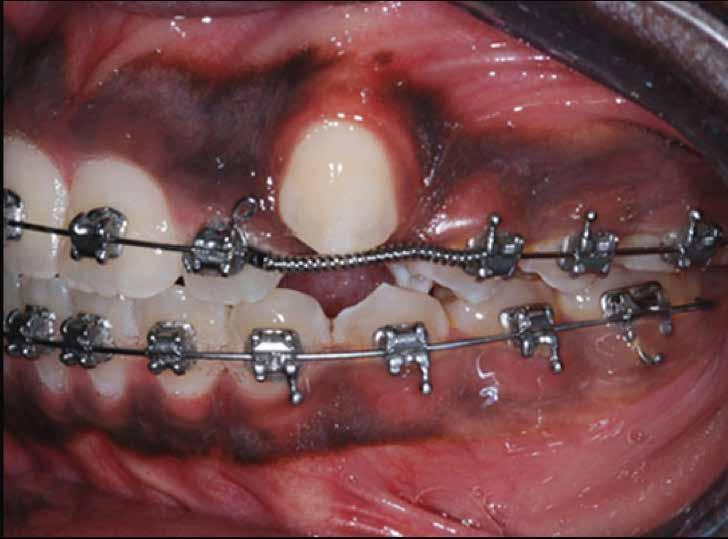

nm-es hullámhosszon pulzáló üzemmódban alkalmazott lézert használtunk (LaserHF standard, Hager & Werken). A teljesítménye 3 W, az aktív ciklus-idő 50%-os, a vezetőszál átmérője pedig 0,4 mm volt (2. ábra). A lézert 150 másodpercen keresztül alkalmaztuk. A fogat borító lágyrészek eltávolítását követően egy láncos brekettet rögzítettünk a metszőfog bukkális felszínére. A műtétet követően nem tapasztaltunk vérzést, nem alakult ki oedema, valamint a páciens sem számolt be fájdalom vagy bármely egyéb kellemetlenség fennállásáról. A felszabadítást követően a páciens minden hónapban háromszor jelent meg a felszabadított területre ránövő lágyrészek és az íny lézeres eltávolítása céljából. A beavatkozások során ugyanazt a lézer készüléket használtuk, mint amivel a felszabadítást végeztük. Közvetlenül a felszabadítást követően megkezdtük a fog finom extrudálását a láncos breketthez kötött füzérgumi segítségével.

2. ábra: Az impaktált fog lézerrel asszisztált sebészi feltárása. 3. ábra: A kezelés megkezdését követő 15. hónapban megfigyelhető a sikeres felszabadítást, fogmozgatást és pozicionálást követően látható állapot.